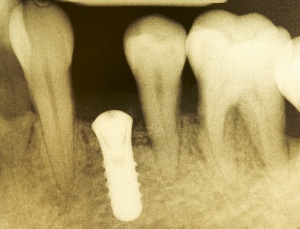

Dies lässt sich exemplarisch auch im folgenden Fall zeigen: Ein männlicher Patient mit der Diagnose einer generalisierten aggressiven Parodontitis (32 Jahre) befand sich zunächst in einer systematischen antiinfektiösen nichtchirurgischen Parodontitistherapie mit begleitender systemischer Antibiose. An der nachfolgenden unterstützenden Parodontitistherapie nahm er jahrelang teil (2007 – heute) und wies eine sehr gute Compliance auf. Im Oktober 2012 erfolgte durch mich die Implantation regio 34. Ein Jahr post implantationem zeigen sich unverändert kein periimplantärer Knochenabbau sowie klinisch gesunde Gingivaverhältnisse und physiologische Sondiertiefen (Abb. 18).